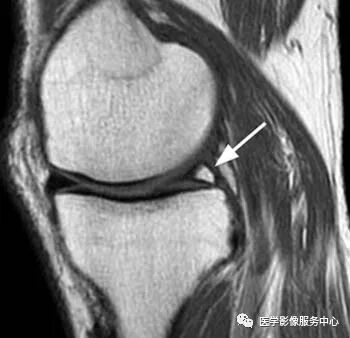

横韧带是连接内、外侧半月板前角的韧带,在矢状位片上,内侧半月板前角附着部位于横韧带正前方,而外侧半月板前角位于横韧带后方。易误诊为前角撕裂。

白色箭头所标记为膝横韧带

白色箭头所指为横韧带,外侧半月板前角位于横韧带后方

膝横韧带经常容易被误诊为半月板前角撕裂或损伤,我们需要知道有这根韧带,而且要知道它特殊的解剖位置和半月板的形态是否正常,从而与半月板前角鉴别;